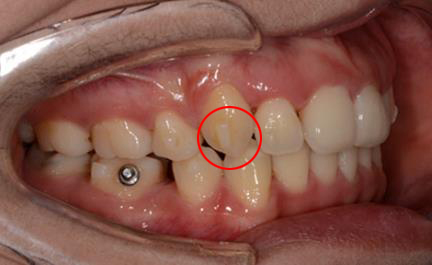

(2) 钢丝扎嘴(结扎丝与弓丝):若为结扎丝扎嘴,可以采用圆钝物体比如筷子、铅笔头等将结扎丝重新压到弓丝的下方操作过程中力量不要过大,避免托槽松动脱落。若为主弓丝扎嘴,则建议使用粘膜保护蜡或口香糖包裹扎嘴部位(如上图所示